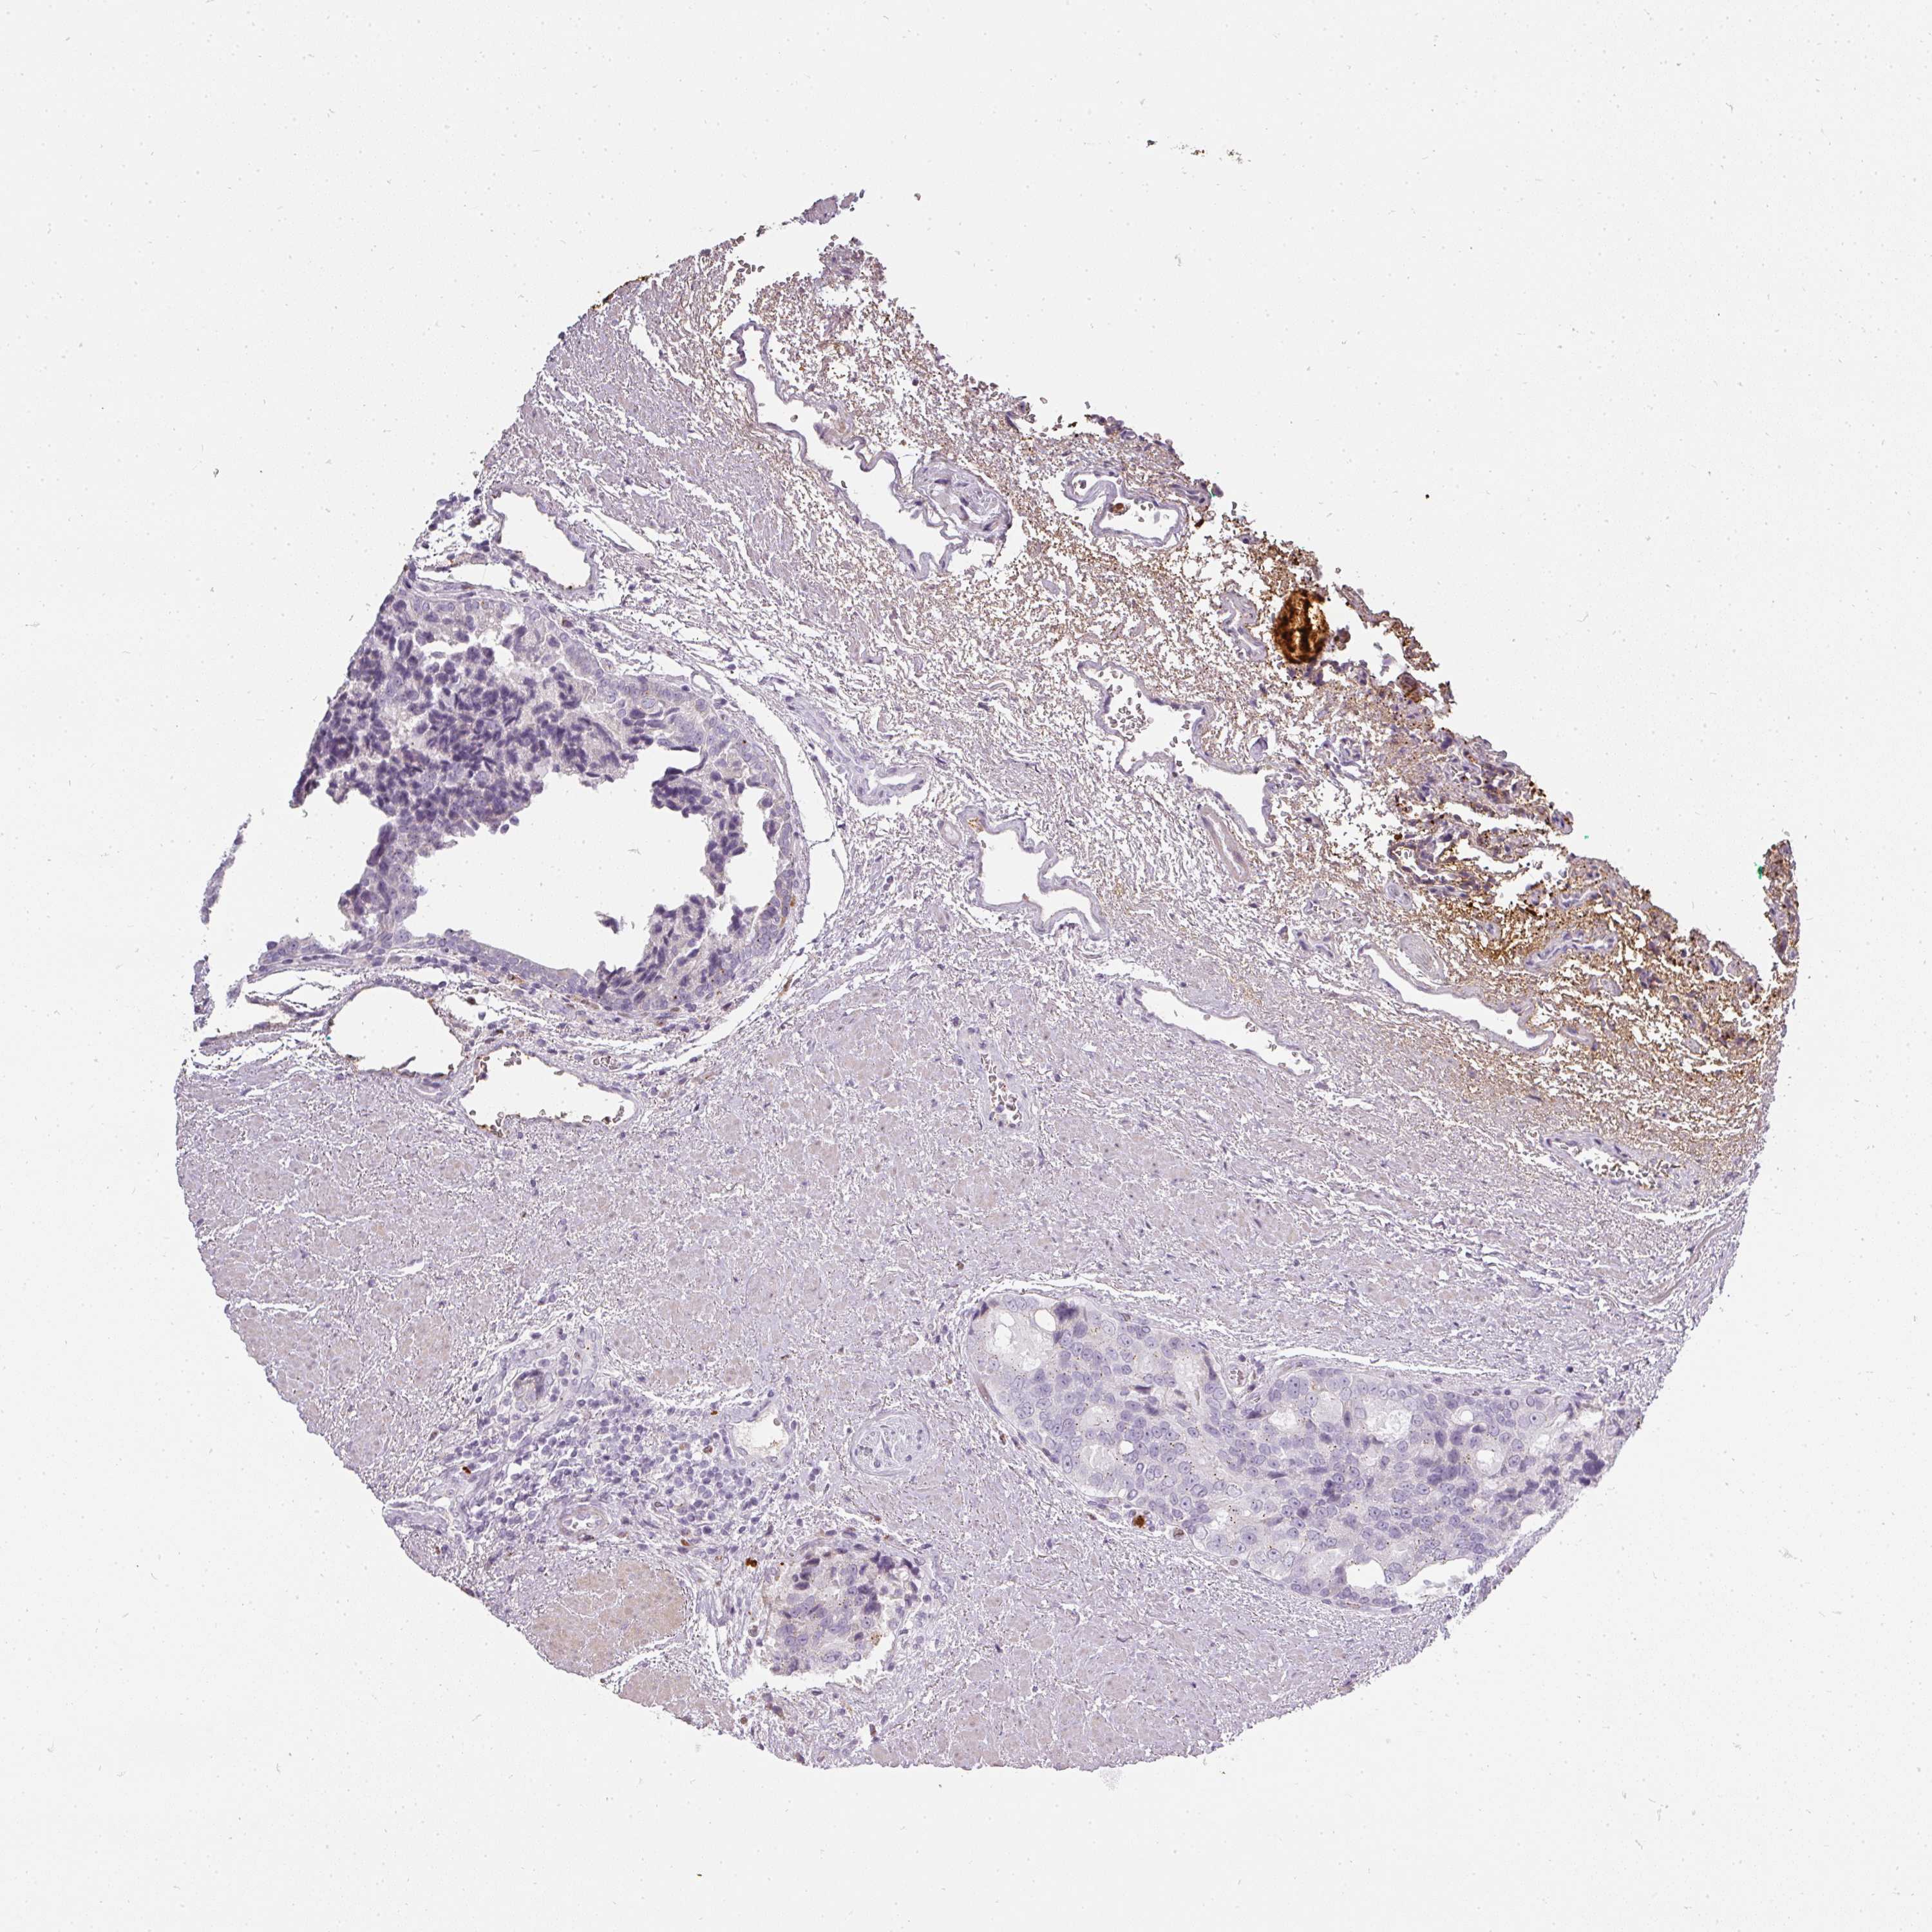

PROSTATE CANCER - Protein expressioni

A mouse-over function shows sample information and annotation data. Click on an image to view it in a full screen mode. Samples can be filtered based on level of antibody staining by selecting one or several of the following categories: high, medium, low and not detected. The assay and annotation is described here.

Antibody stainingi

Antibody staining in the annotated cell types in the current human tissue is reported as not detected, low, medium, or high, based on conventional immunohistochemistry profiling in selected tissues. This score is based on the combination of the staining intensity and fraction of stained cells.

Each image is clickable and will lead to virtual microscopy that enables deeper exploration of all samples and also displays staining intensity scores, fraction scores and subcellular localization as well as patient and tissue information for each sample.

Antibody HPA051360

Staining

High

Medium

Low

Not detected

Intensity

Strong

Moderate

Weak

Negative

Quantity

>75%

75%-25%

<25%

None

Location

Nuclear

Cytoplasmic/membranous

Cytoplasmic/membranous,nuclear

Adenocarcinoma, NOS

Adenocarcinoma, High grade

Adenocarcinoma, Low grade